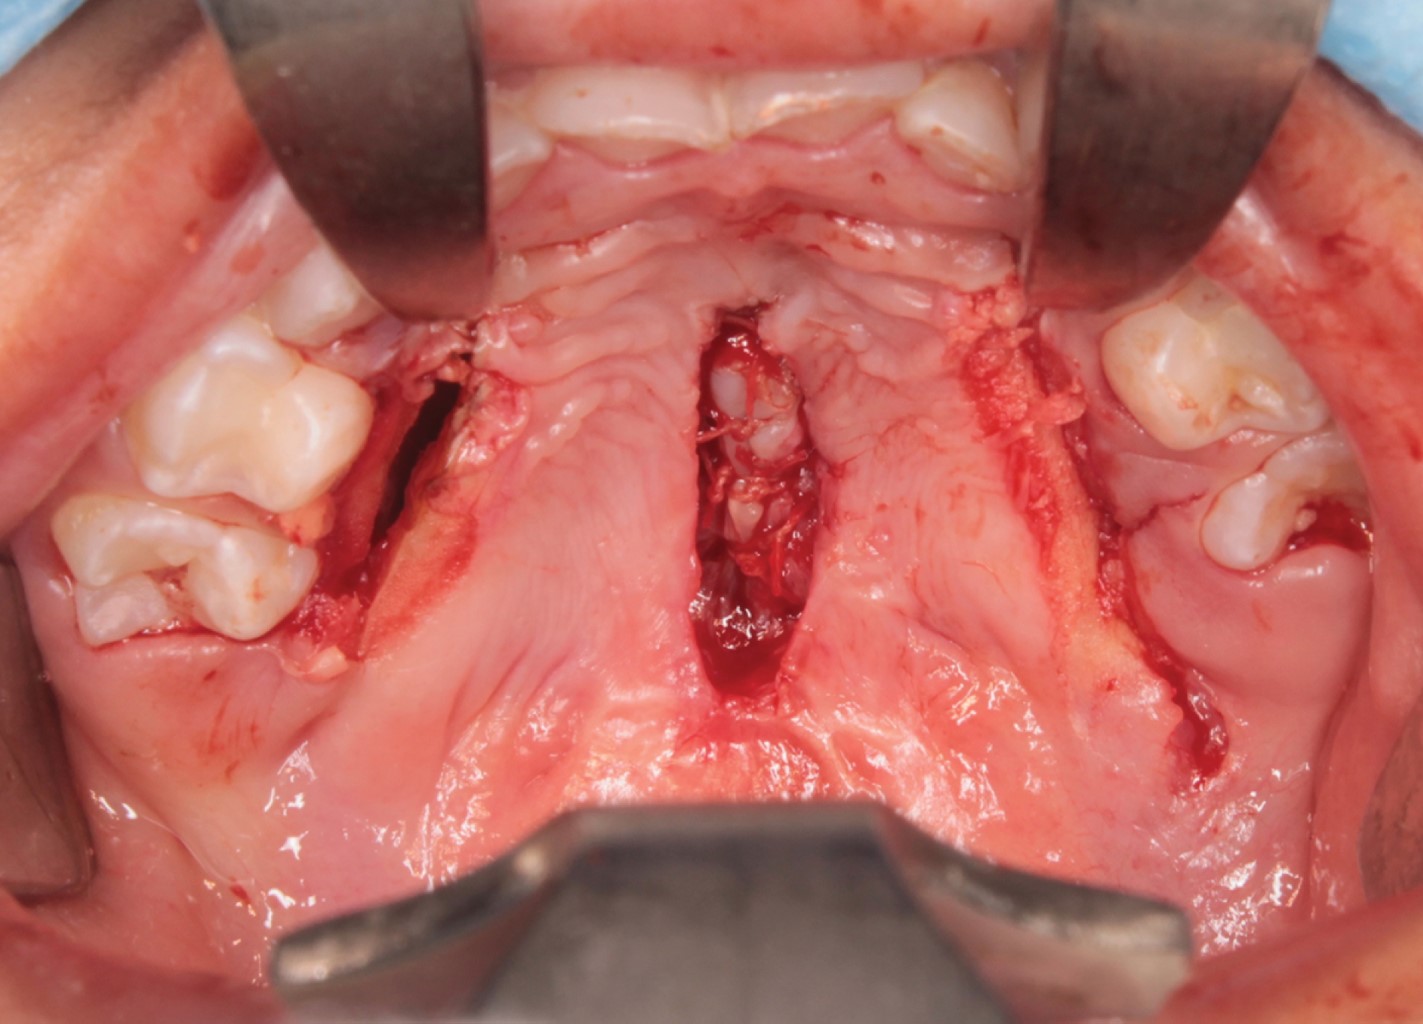

Después de seis meses de la palatoplastia primaria, se decidió realizar cierre de fístula. Con el paciente bajo anestesia general balanceada, se efectuaron incisiones en los bordes de la fístula, separando las capas nasal y oral, cerrando en dos planos, utilizando un colgajo de mucosa oral invertida para la capa nasal y reclutando tejidos locales para un colgajo mucoperióstico utilizado para el cierre de la capa oral, apoyado de incisiones relajantes. El procedimiento se llevó a cabo sin complicaciones ni eventualidades (Figuras 4 y 5). El paciente fue dado de alta; acudió a controles postoperatorios después de una semana, un mes y seis meses, cursando con una cicatrización adecuada. Actualmente cuenta con dos años de evolución, se encuentra asintomático y sin datos de recidiva de fístula palatina (Figura 6).

Figura 5